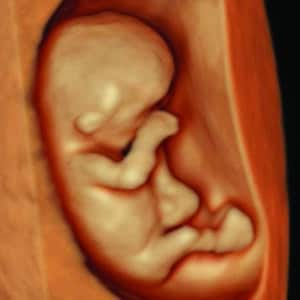

Explore our Photo Gallery and see the real results from Knit 4D Ultrasound. Every image you see  from 2D, 3D, 4D, to HD live ultrasounds  was captured by our highly trained team using our state-of-the-art ultrasound machine. We can begin creating amazing 3D/4D keepsake images as early as 8 weeks, giving you a beautiful first look at your baby.